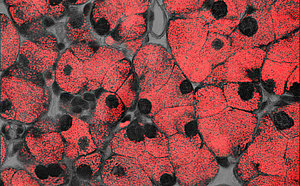

Pancreas_acinar_cells_613_379.jpg

Azinuszellen des Pankreas